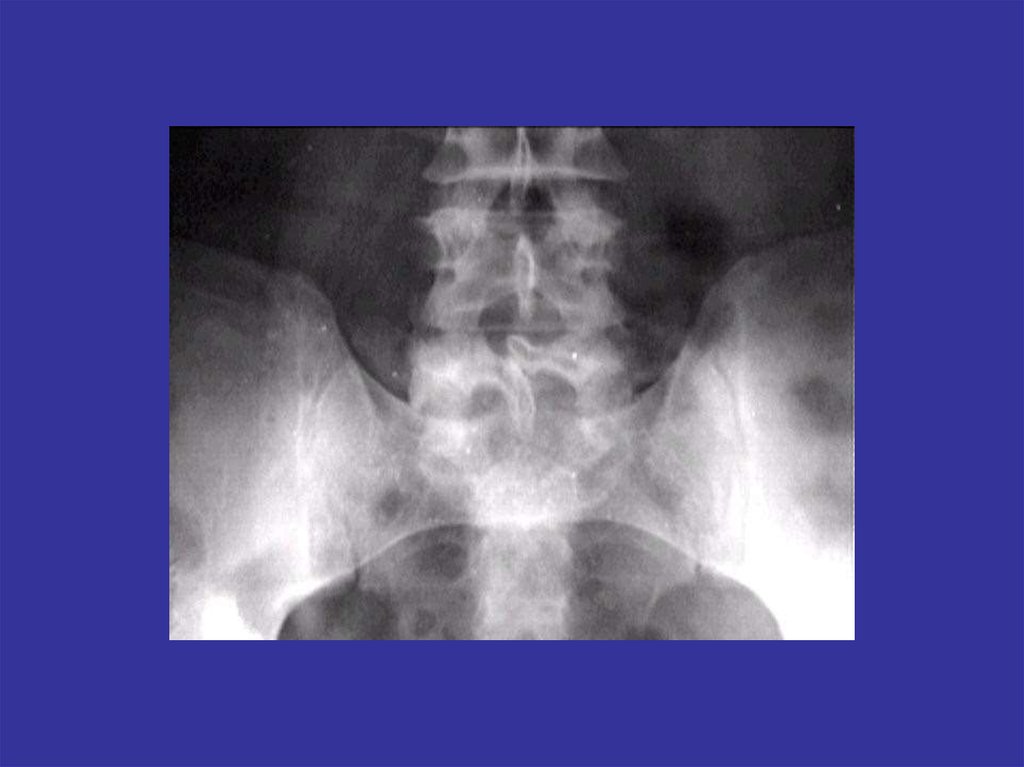

Аномалии развития позвоночника